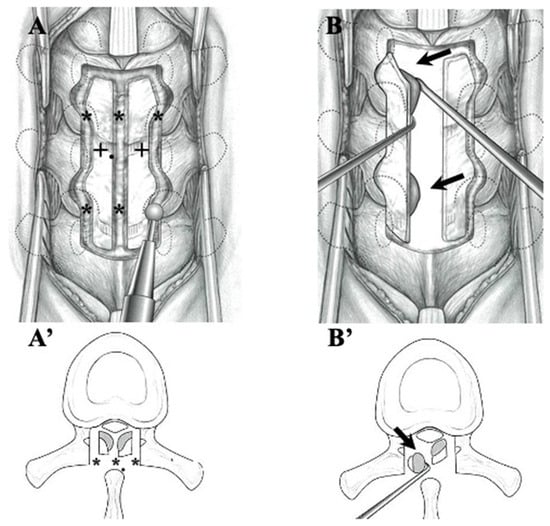

2.2.2. Surgical Indication and Procedure (Figure 1 and Figure 2, Table 4)

4.3. Surgical Treatments and Outcomes in CLF and OLF (Figure 1 and Figure 2; Table 4)